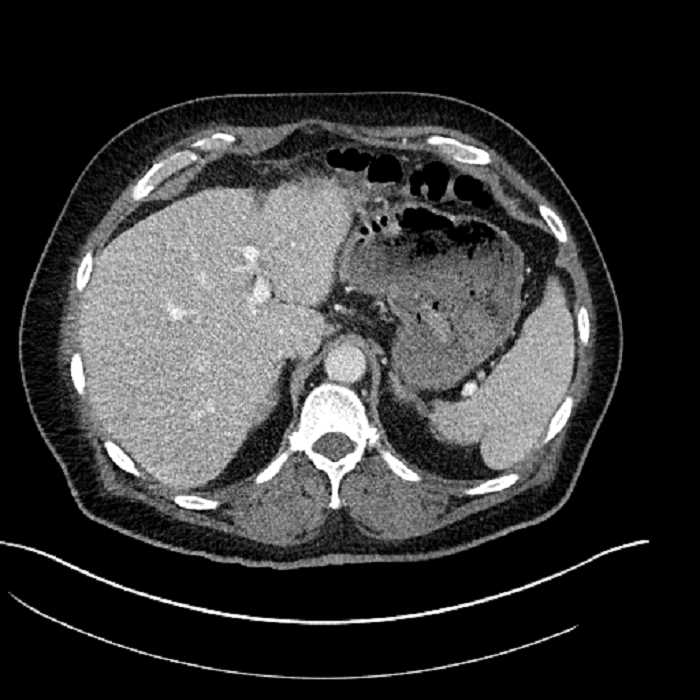

Age: 63

Sex: Male

Indication: Abdominal pain

• Large fluid density structure in hepatic segments 7 and 8 measuring 10 x 7 x 7 cm with internal septation and circumferential ill-defined low density compatible with edema

• Peripherally enhancing subcapsular collections along the anterior margin of the left hepatic lobe measuring 3 x 1 cm and 2 x 1 cm

• Clearly marginated fluid density structure in segment 7 and several other scattered tiny hypodensities, which likely represent cysts

Acute sigmoid diverticulitis complicated by a small contained perforation and a large abscess in the right hepatic lobe. Additional small subcapsular abscesses along the anterior margin of the left hepatic lobe.

• The classic CT imaging appearance is a double target sign with internal low density surrounded by an internal enhancing rim (capsule) and a low density external rim (edema)

Hepatic abscess showing the double target sign with low density internally surrounded by a thin inner enhancing rim (red arrow) and ill-defined outer low density rim (yellow arrow). Blue arrow indicates an internal septation. Red arrows: additional smaller subcapsular abscesses. Red arrow: focal contained perforation associated with diverticulitis.